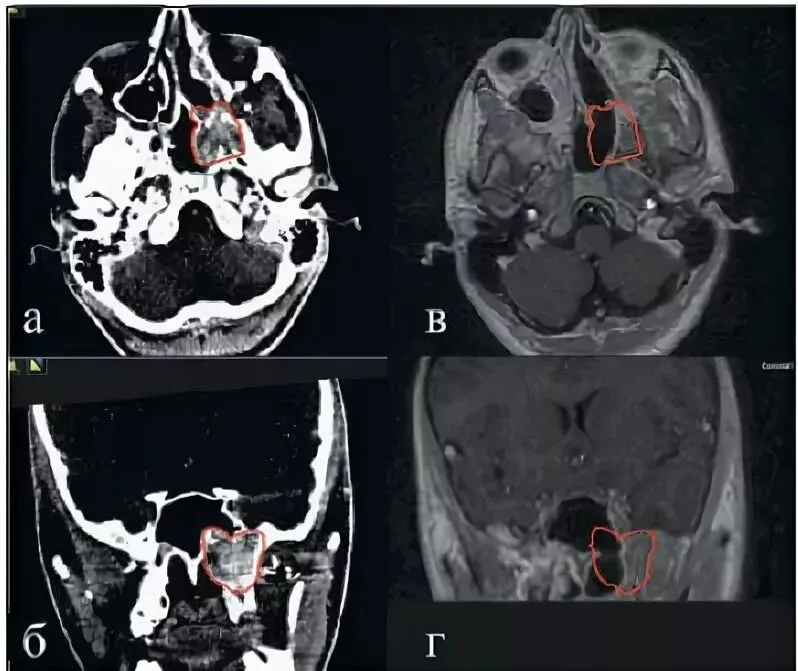

Врачи ЛОР отделения ОДКБ поставили 15-летнему подростку диагноз - опухоль в основании черепа, которая называется "юношеская ангиофиброма". Если эту доброкачественную и быстро растущую опухоль не лечить, пациент может умереть.

Фото: ОДКБ.